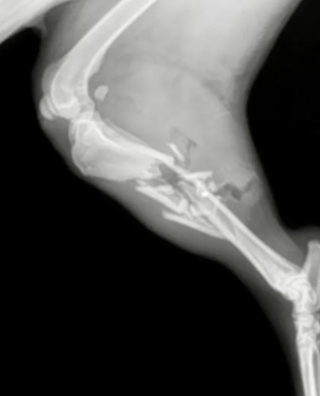

La balle ayant traversé le tibia de la chienne, il fallait agir pour sa survie. L’idée de l’amputation a été évoquée, mais finalement rapidement mise de côté, les vétérinaires ayant une autre idée en tête.

Admise aussitôt en salle de chirurgie, la patte de Susie a été renforcée avec des plaques, des broches et des vis permettant de la maintenir droite. Cette prouesse chirurgicale n’avait qu’un objectif : redonner un jour sa mobilité à la chienne.